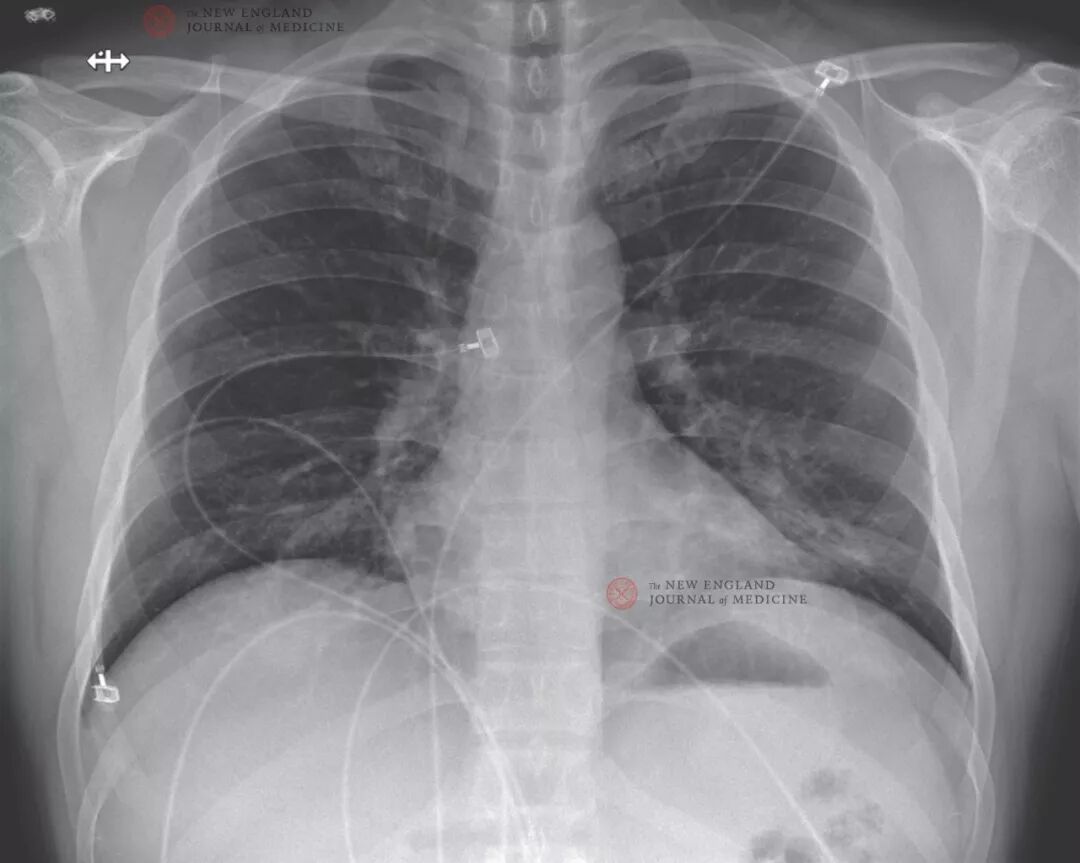

住院第2至5日(发病第6至9日),除出现间歇性发热并伴有心动过速之外,患者生命体征基本平稳。患者仍有干咳,乏力。住院第2日下午,患者排稀便,腹部不适。夜间再次排稀便;采集的粪便和上呼吸道样本,以及鼻咽和口咽拭子经rRT-PCR检测2019-nCoV均呈阳性,血清检测为阴性。自此期间,主要对患者实施支持性治疗。对患者给予对症治疗:根据发热情况给予退热药,包括每4小时650 mg对乙酰氨基酚和每6小时600 mg布洛芬;口服600 mg愈创甘油醚缓解持续咳嗽;住院后6天内大约给予6 L生理盐水补液。由于患者隔离病房最初只允许用床旁设备进行样本检测,患者住院第3日才开始全血细胞计数及血清化学检测。在患者住院的第3日开始进行血常规和生化检测。患者住院第3日和第5日(发病第7日和第9日)实验室结果显示:白细胞减少,轻度血小板减少以及肌酸激酶(CK)水平升高(表1)。此外,肝功能指标也出现异常:ALKP(68 U/L),ALT(105 U/L),AST(77 U/L)和LDH (465 U/L)的水平都在住院的第5日所有升高。鉴于患者反复发热,在住院第4日进行了血培养检测,截至目前未有细菌生长。患者住院第3日(发病第7日)的胸片检查显示没有肺部浸润或其他异常(图3)。然而,在住院第5日晚上(发病第9日)的第二次胸片显示左下肺叶有肺炎迹象(图4)。以上影像学的发现与患者住院第5日晚上开始的呼吸症状改变相吻合,该患者当日呼吸环境空气时的氧饱和度下降至90%。住院第6日给患者行2 L/分鼻导管吸氧。考虑到临床表现的突然变化和发生医院获得性肺炎的可能性,给予万古霉素(1750 mg,然后每8小时静脉注射1 g)和头孢吡肟(每8小时静脉注射一次)治疗。将钙值转换成mmol/L需乘以0.250。将血尿素氮值转换为mmol/L需乘以0.357。将肌酸酐值转换为μmol/L需乘以88.4。将总胆红素值转换为μmol/L需乘以17.1.![]()

图3. 后前位及侧位胸片,2020年1月22日(发病第7日,住院第3日)。胸内片平扫无异常提示。